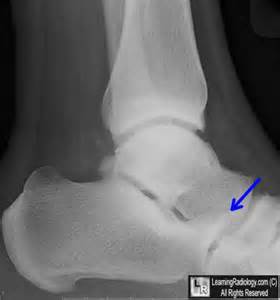

hawkins sign 中壢高正雄骨科診所

hawkins sign

霍金斯標識.是在距骨圓頂指示存活力6至8週的距骨骨折後的軟骨下透亮頻帶。它是在前後視圖中可見的,但很少出現在側位片。

如果全部或部分呈現陽性霍金斯符號被檢測到,這是不可能在損傷後的稍後階段發展成缺血性壞死.是一種很好判斷方法.